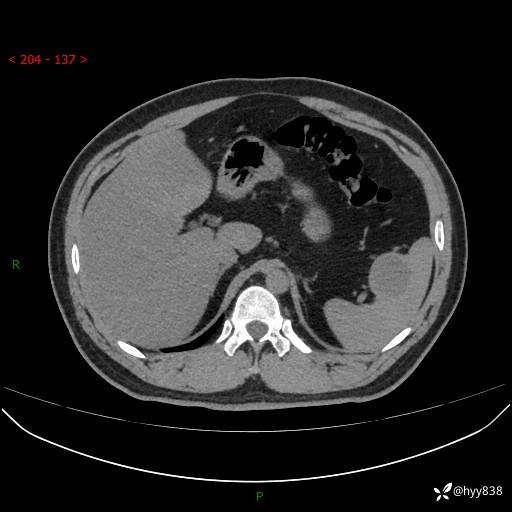

【患者信息】:31岁/男

【主诉】:超声发现脾脏肿物,为进一步诊治来我院,门诊以“脾脏占位”收入院

【检查】:上腹部CT平扫+增强